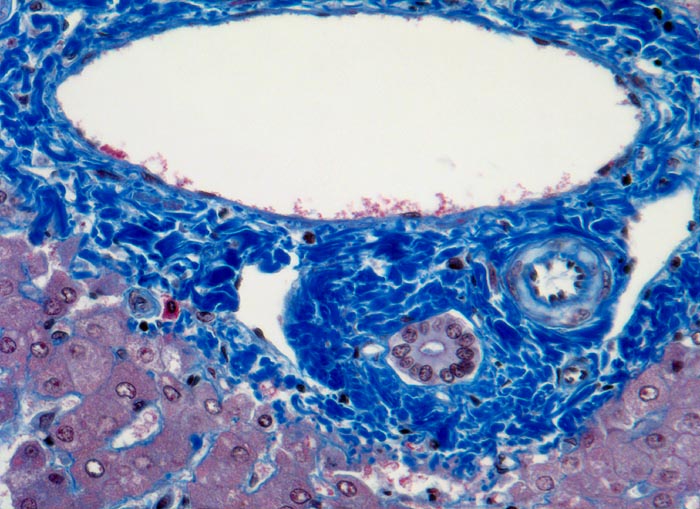

Unbehandelt ist die Prognose sehr schlecht. Sie wird im wesentlichen bestimmt durch Tumorgröße, Zahl der Tumorherde, Gefäßinvasion (> 4474), Vorliegen einer Pfortaderthrombose, Höhe des Alpha-Fetoproteins (AFP) im Serum und den Schweregrad der Leberfunktionsstörung. Die durchschnittliche Überlebenszeit symptomatischer Patienten beträgt meist nur einige Monate.

• Innerhalb des Tumors Blutgefässe, aber keine Portalfelder.

• Sinusoidartige Blutgefässe mit Endothelauskleidung verlaufen zwischen den Trabekeln und den Pseudodrüsen.